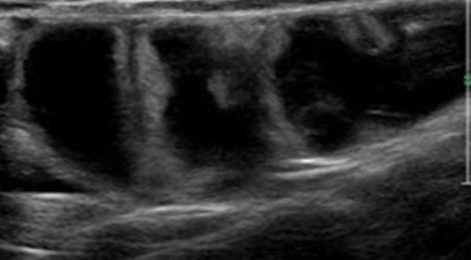

Bowel obstruction